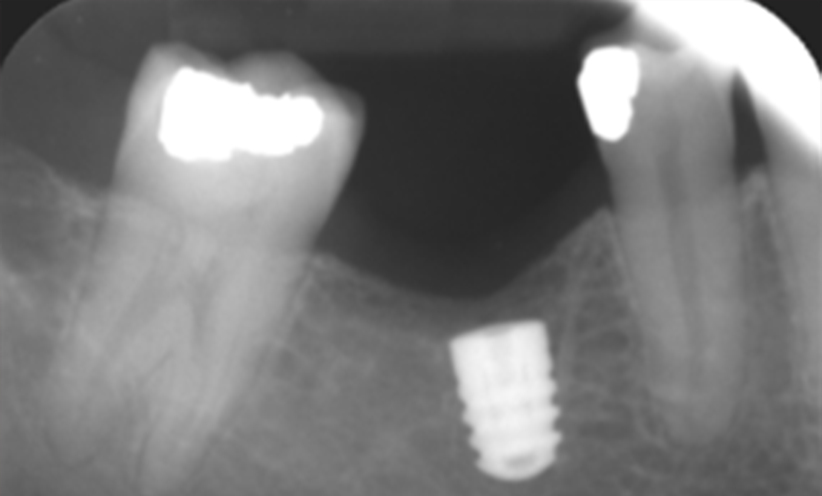

Case 3